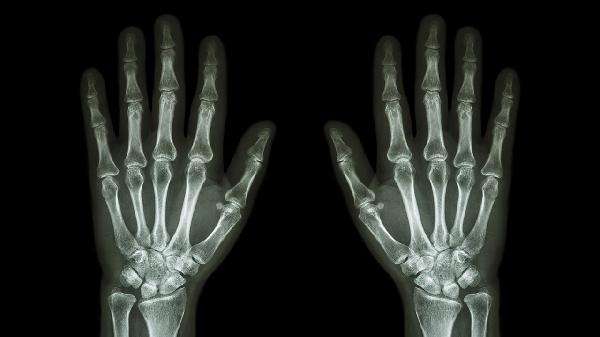

手指關(guān)節(jié)無緣無故腫痛,到底什么原因

手指關(guān)節(jié)無緣無故腫痛可能與骨關(guān)節(jié)炎、類風(fēng)濕關(guān)節(jié)炎、痛風(fēng)性關(guān)節(jié)炎、外傷或感染性關(guān)節(jié)炎等因素有關(guān)。建議及時(shí)就醫(yī)明確診斷,避免延誤治療。

骨關(guān)節(jié)炎多見于中老年人,與關(guān)節(jié)軟骨退化有關(guān)。表現(xiàn)為晨起關(guān)節(jié)僵硬,活動后腫痛減輕,X線可見關(guān)節(jié)間隙變窄??勺襻t(yī)囑使用硫酸氨基葡萄糖膠囊、雙醋瑞因膠囊等軟骨保護(hù)劑,配合局部熱敷緩解癥狀。